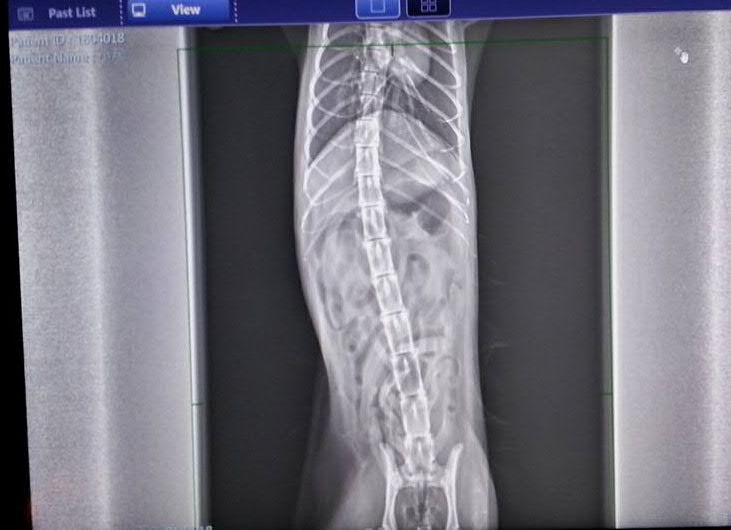

主題: 腎臟積水的三腳小居 申請者姓名: 臺北市支持流浪貓絕育計劃協會 花色: 申請日期: 2018-05-09 12:27:43 申請者部落格: 申請者臉書網址: http://admin.tnrtw.org/hospice_add.php 所在縣市/合作醫院: 台北市/澄諾動物醫院 治療費用: 19629元 需求人數: 43人 已結案 (2024-06-01 13:12:27) 報名人員: 柔(已付款)、Jube(已付款)、Jube(已付款)、EPT(已付款)、Lannie Lin x3(已付款)、YLC(已付款)、littlecut(已付款)、Naommi x2(已付款)、胖肯尼(已付款)、小伶 x6(已付款)、Janney x2(已付款)、Isabel Liu x10(已付款)、壞壞(已付款)、Moon x2(已付款)、Sugar Hung(已付款)、monilovecat(已付款)、Isabel Liu(已付款)、Isabel Liu x4(已付款)、Sol x2(已付款)、Tzu Ning Kuo(已付款)、 候補人員: 動物病情說明: 4/16 小居看診 澄諾

體重:2.1kg

體溫:36.8

看診情形

口腔檢查看到右邊牙齦有處類似組織爛肉,已發出不好味道,體重很輕, 體溫過低。

醫生為她抽血檢驗,稍晚會告知檢驗結果,可能視情況為她上點滴、鎮靜做進一步檢查及醫療,所以先將小居留院,照X光、血檢、尿檢、超音波等檢查,醫師診斷小居口腔的潰爛可能是腎臟問題引起的,有水腎現象。動物近況說明: 後轉泌尿科專科醫師治療 持續住院中